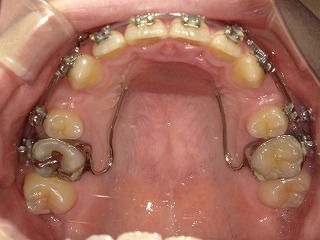

上顎もわずかですが寄ってきている兆候がわかります。

12月には下顎はほぼ閉じているのではないかとひそかに期待しております。(・∀・)

こちら今回の写真です

こちら前回の写真です